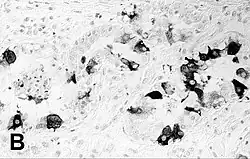

| Immunohistochemical staining of the lung of a seal with PDV infection | |